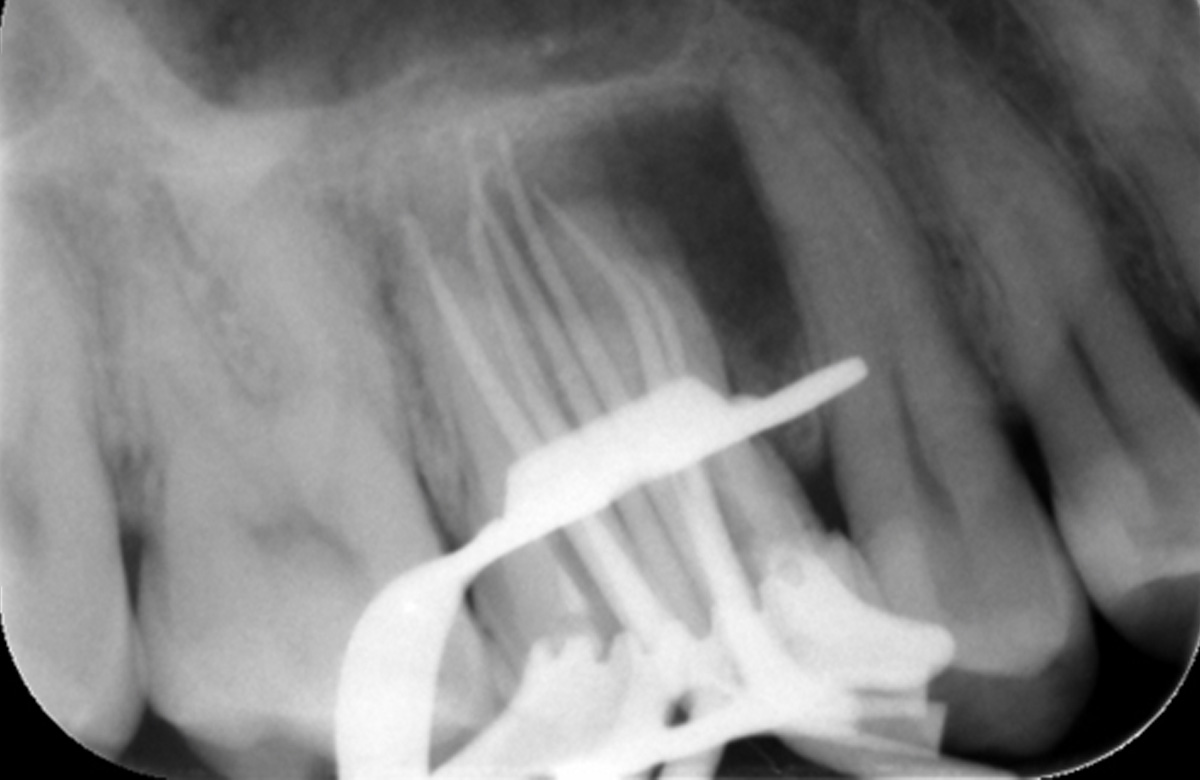

| Tooth | 16 |

Pre operative periapical radiograph of the tooth 16

| Diagnosis | Previously endodontically treated tooth with persisting chronic apical periodontitis |

| Dental history | Patient has had previous root canal treatment over 5 years ago |

| Clinical evaluation | Tooth that is tender to percussion & palpation. Small fluctuant swelling associated with buccal alveolar mucosa |